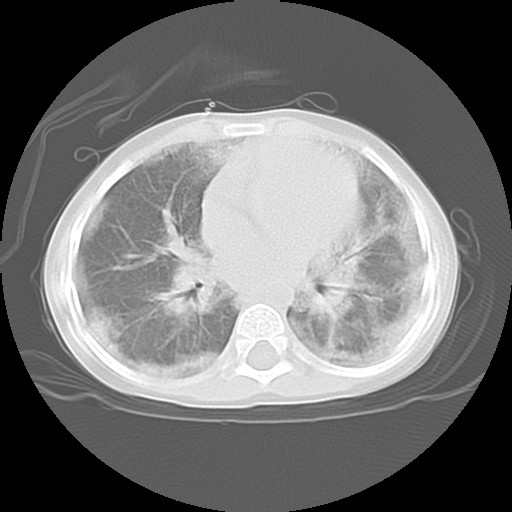

![]() Figure 4b |